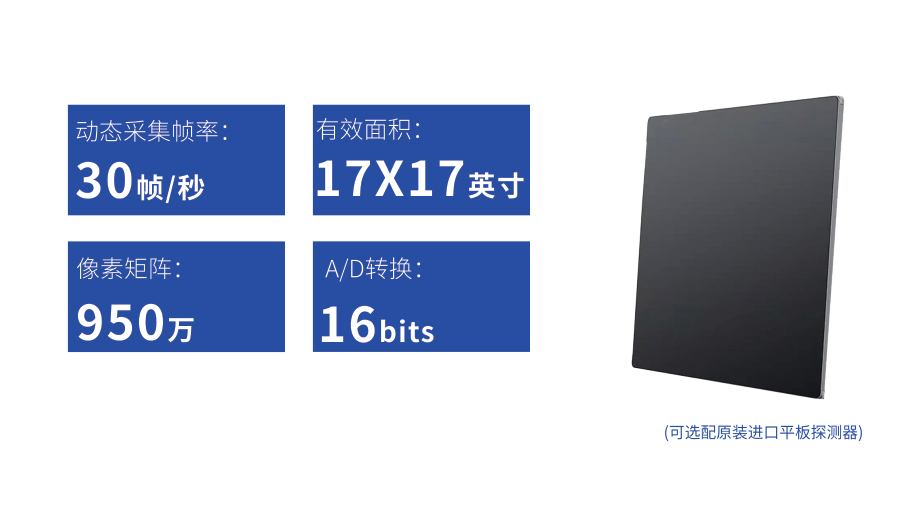

● 17*17英寸的超高清像素动态平板探测器,更大的视野范围,无需移动即可观察整个动态过程,避免拖尾、噪声对图像的影响;

● 高效动态平板技术,图像不会有几何畸变,提供高分辨率和精确的图像,为医生临床诊断提供精准依据;

● 最高帧速可达30帧/秒,动态采集清晰流畅,避免漏诊、误诊情况的发生;